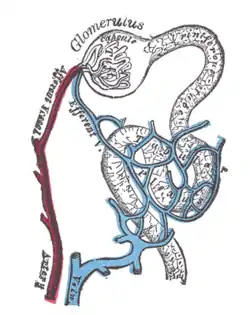

Diagram (left) of a long juxtamedullary nephron and (right) of a short cortical nephron. The left nephron is labelled with six named nephron segments. Also labelled is the collecting duct, mislabelled the "collection duct"; it is the last part of the nephron. | |

The nephron is the minute or microscopic structural and functional unit of the kidney. It is composed of a renal corpuscle and a renal tubule. The renal corpuscle consists of a tuft of capillaries called a glomerulus and a cup-shaped structure called Bowman's capsule. The renal tubule extends from the capsule. The capsule and tubule are connected and are composed of epithelial cells with a lumen. A healthy adult has 1 to 1.5 million nephrons in each kidney.[1]: 22 Blood is filtered as it passes through three layers: the endothelial cells of the capillary wall, its basement membrane, and between the foot processes of the podocytes of the lining of the capsule. The tubule has adjacent peritubular capillaries that run between the descending and ascending portions of the tubule. As the fluid from the capsule flows down into the tubule, it is processed by the epithelial cells lining the tubule: water is reabsorbed and substances are exchanged (some are added, others are removed); first with the interstitial fluid outside the tubules, and then into the plasma in the adjacent peritubular capillaries through the endothelial cells lining that capillary. This process regulates the volume of body fluid as well as levels of many body substances. At the end of the tubule, the remaining fluid—urine—exits: it is composed of water, metabolic waste, and toxins.

The interior of Bowman's capsule, called Bowman's space, collects the filtrate from the filtering capillaries of the glomerular tuft, which also contains mesangial cells supporting these capillaries. These components function as the filtration unit and make up the renal corpuscle. The filtering structure (glomerular filtration barrier) has three layers composed of endothelial cells, a basement membrane, and podocytes (foot processes). The tubule has five anatomically and functionally different parts: the proximal tubule, which has a convoluted section the proximal convoluted tubule followed by a straight section (proximal straight tubule); the loop of Henle, which has two parts, the descending loop of Henle ("descending loop") and the ascending loop of Henle ("ascending loop"); the distal convoluted tubule ("distal loop"); the connecting tubule, and the last part of nephron the collecting ducts. Nephrons have two lengths with different urine-concentrating capacities: long juxtamedullary nephrons and short cortical nephrons.

Length difference

Cortical nephrons (the majority of nephrons) start high in the cortex and have a short loop of Henle which does not penetrate deeply into the medulla. Cortical nephrons can be subdivided into superficial cortical nephrons and midcortical nephrons.[8]

Juxtamedullary nephrons start low in the cortex near the medulla and have a long loop of Henle which penetrates deeply into the renal medulla: only they have their loop of Henle surrounded by the vasa recta. These long loops of Henle and their associated vasa recta create a hyperosmolar gradient that allows for the generation of concentrated urine.[9] Also the hairpin bend penetrates up to the inner zone of medulla.[10]

Juxtamedullary nephrons are found only in birds and mammals, and have a specific location: medullary refers to the renal medulla, while juxta (Latin: near) refers to the relative position of the renal corpuscle of this nephron - near the medulla, but still in the cortex. In other words, a juxtamedullary nephron is a nephron whose renal corpuscle is near the medulla, and whose proximal convoluted tubule and its associated loop of Henle occur deeper in the medulla than the other type of nephron, the cortical nephron.

The juxtamedullary nephrons comprise only about 15% of the nephrons in the human kidney.[1]: 24 However, it is this type of nephron which is most often depicted in illustrations of nephrons.

In humans, cortical nephrons have their renal corpuscles in the outer two thirds of the cortex, whereas juxtamedullary nephrons have their corpuscles in the inner third of the cortex.[1]: 24